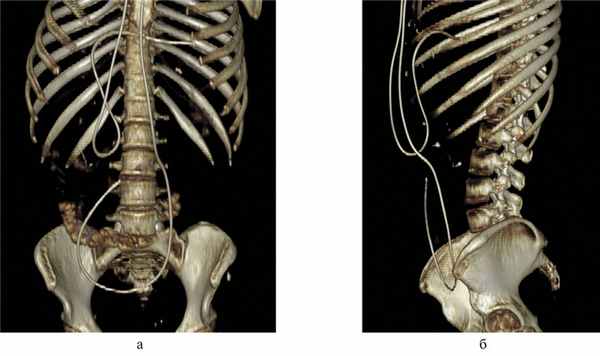

По данным КТ органов брюшной полости с контрастированием, в брюшной полости определяются вентрикуло-перитонеальные шунты, дистальный конец одного определяется в левом поддиафрагмальном пространстве, дистальный конец другого — в правом мезогастрии (рис. 3). Рис. 3. Компьютерная томография органов брюшной полости. а, б — визуализированы вентрикуло-перитонеальные шунты.